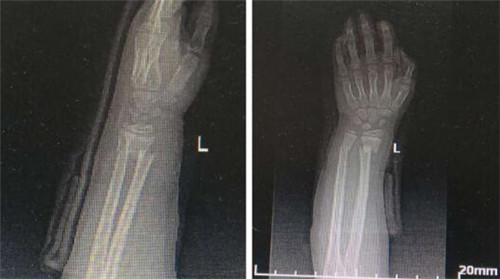

2月27日,我院手术麻醉科主治医师钟永慧在对口支援医院—渭南市第二医院,实施了渭南市首例超声引导下臂丛神经阻滞麻醉行尺桡骨骨折切开复位内固定术。

患者为11岁男孩,因摔伤致左尺桡骨骨折,进入手术室后,为其连接监护开放静脉通路,经再次充分沟通后,在超声引导下行肌间沟(1%利多卡因+0.375%左布比卡因混合液7ml)+腋下(1%利多卡因+0.375%左布比卡因混合液8ml)臂丛神经阻滞。单纯的肌间沟止血带耐受较好,但尺侧阻滞效果差;腋下前臂阻滞效果好,但患者不能耐受止血带。整个麻醉操作过程顺利,效果确切,术程平稳。